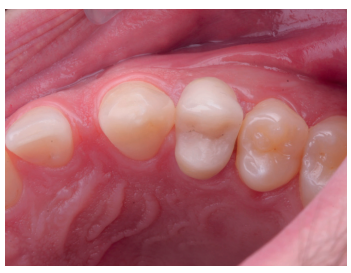

Se presenta en el Máster en Cirugía Oral, Implantología y Periodoncia de la Universidad Alfonso X El Sabio (Madrid, España) un paciente de 24 años derivado para exodoncia del primer premolar superior izquierdo y colocación inmediata de implante debido a una fractura corono-radicular como consecuencia de caries asintomática, con margen distal 2 mm subgingival y limitada estructura remanente (Figuras 1 y 2). Después de un estudio completo del caso, en colaboración con el Máster en Endodoncia de la misma facultad, se planificó la realización de la extrusión quirúrgica, endodoncia y posterior rehabilitación del diente. Dentro de este estudio resultaron de vital importancia las pruebas radiológicas, compuestas por radiografías periapicales y CBCT, que confirmaron la compatibilidad de la anatomía radicular con la realización de una extrusión mínimamente traumática.

con fractura corono-radicular.

fractura corono-radicular.